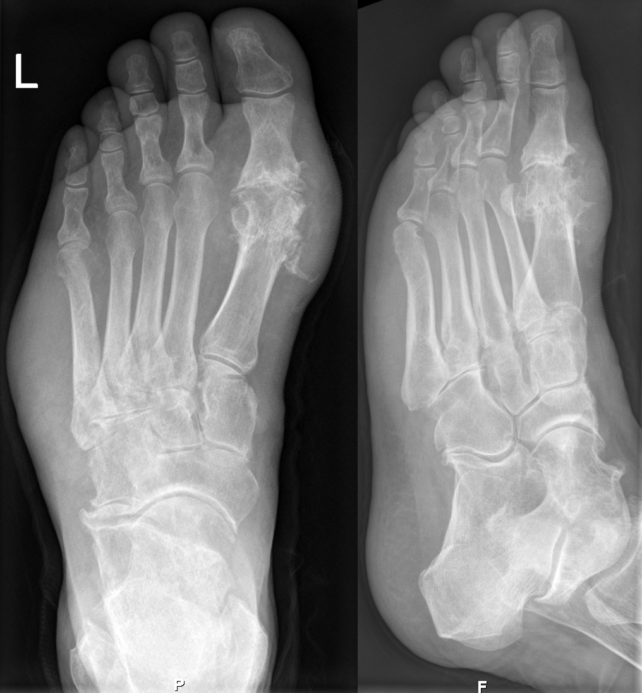

Huge Study Shows Where Gout Comes From, And It Isn't What We ThoughtGout on X-rays of a left foot in the metatarsal-phalangeal joint of the big toe. (Hellerhoff/CC BY-SA 3.0/Wikimedia Commons)